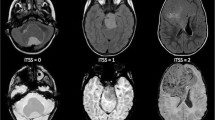

Childhood brain tumors show great histological variability. The goal of this retrospective study was to assess the diagnostic accuracy of multimodal MR imaging (diffusion, perfusion, MR spectroscopy) in the distinction of pediatric brain tumor grades and types. Seventy-six patients (range 1 month to 18 years) with brain tumors underwent multimodal MR imaging. Tumors were categorized by grade (I–IV) and by histological type (A–H). Multivariate statistical analysis was performed to evaluate the diagnostic accuracy of single and combined MR modalities, and of single imaging parameters to distinguish the different groups. The highest diagnostic accuracy for tumor grading was obtained with diffusion–perfusion (73.24 %) and for tumor typing with diffusion–perfusion–MR spectroscopy (55.76 %). The best diagnostic accuracy was obtained for tumor grading in I and IV and for tumor typing in embryonal tumor and pilocytic astrocytoma. Poor accuracy was seen in other grades and types. ADC and rADC were the best parameters for tumor grading and typing followed by choline level with an intermediate echo time, CBV for grading and Tmax for typing. Multiparametric MR imaging can be accurate in determining tumor grades (primarily grades I and IV) and types (mainly pilocytic astrocytomas and embryonal tumors) in children.